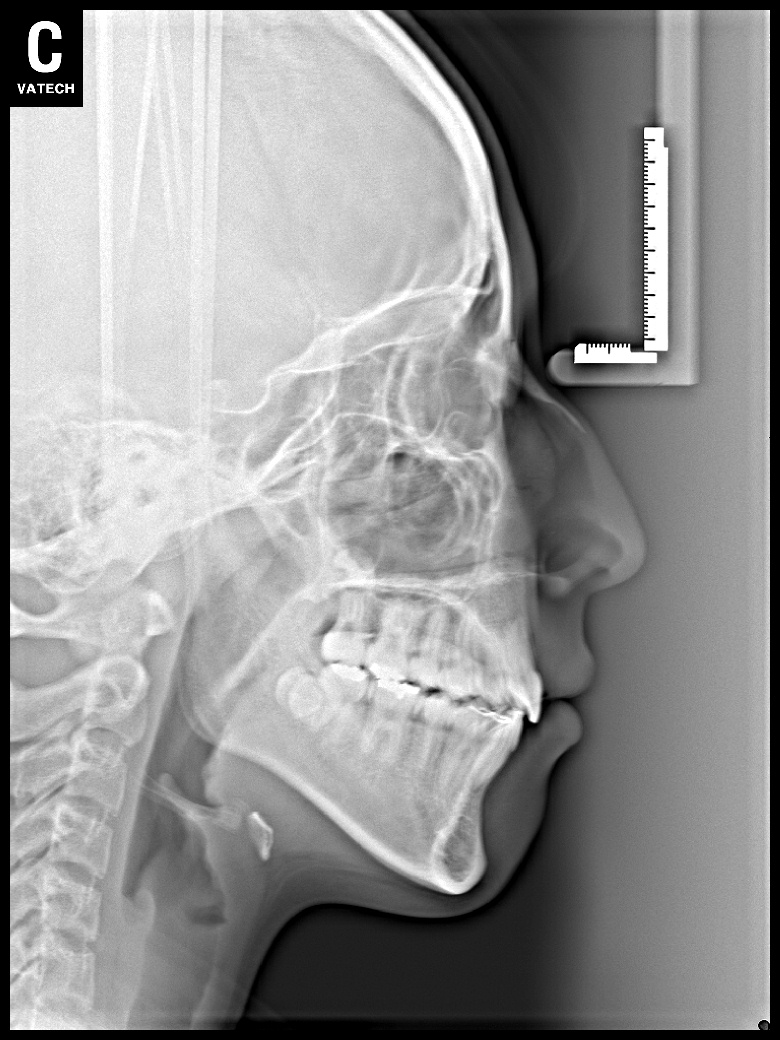

치료 후 사진입니다.